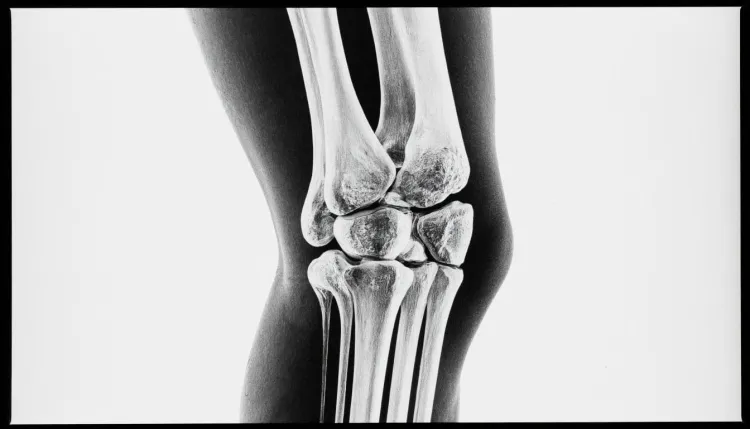

МРТ коленного сустава – это современный метод диагностики, который позволяет получить детализированные изображения структуры колена. Благодарите высокую точность и информативность, данный вид обследования широко применяется в медицине. Он помогает врачам точно выявить патологии и причины болей в колене, что способствует эффективному лечению.

Что может выявить МРТ?

Метод позволяет диагностировать ряд заболеваний и состояний, включая:

- Повреждения связок – разрывы или растяжения передней и задней крестовидных связок.

- Менископатии – трещины и другие поражения мениска, которые могут вызывать боль и ограничивать движение.

- Дегенеративные изменения – патологии, такие как остеоартрит, которые могут привести к разрушению хрящевой ткани.

- Воспалительные заболевания – артриты, в том числе ревматоидный артрит, характеризующиеся воспалением сустава.

- Кисты и опухоли – наличие различных образований, включая кисты Бейкера и опухоли мягких тканей.

- Инфекционные процессы – острые инфекционные состояния, которые могут осложнять течение заболеваний.

Обследование дает возможность врачу получить четкую и детализированную картину состояния сустава, что способствует назначению целенаправленного лечения.